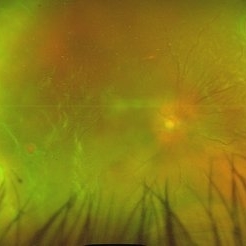

Secondary Pigmentary Degeneration of Retina

Secondary Pigmentary Degeneration of Retina

Jul 18 2025 by Kimberly Wakester

Optomap RGB and AF of an 63-year-old man with secondary pigmentary degeneration of the retina. Patient's Spark genetic testing revealed heterozygous mutations of unknown significance in LRP5, COL18A1, CPLANE1, SLC24A1 and VCAN. Clinical findings most consistent with Wagner's Syndrome (VCAN mutation, autosomal dominant). Will continue follow up care every 6 months with dilated exam and repeat OCT and Optos imaging .

Photographer: Kimberly Wakester, COA, OCT-C

Imaging device: Optos California

Condition/keywords: secondary pigmentary degeneration, Wagner disease